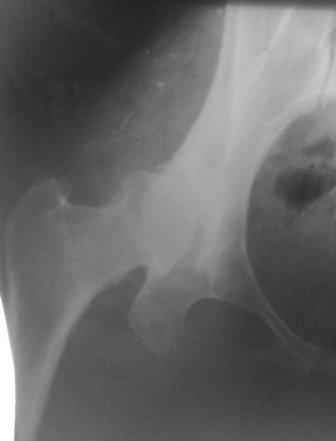

Типичная концовка проигнорированного диспластического состояния сустава. Дисплазия тазобедренного сустава часто встречающаяся патология у жителей Центральной Азии вследствие тугого пеленания в детстве. Традиционно ребенок находится в течение дня в так называемой кроватке "бешик", удобной в быту, но она впоследствии приводит к недоразвитию тазобедренного сустава.

У женщин болезнь клинически проявляется после беременности болями в суставе. Но во время беременности из-за невозможности рентген обследования проблема игнорируется, и упускается время. После беременности симптомы исчезают, и проявляются во время следующей беременности или после увеличения веса.

Это первые признаки начала деструкции сустава, и возможно, аналгетики помогут для купирования болей, но в течение очень короткого времени от сустава ничего не останется, и в дальнейшем останется только артропластика.

Коллеги правильно подсказывают, что варизация ухудшит биомеханику сустава.

При более сохранном суставе от дальнейшего разрушения можно было бы сохранить только периориентацией нагрузки на сустав - Периацетабулярной Остеотомией .

Данный сустав в начальной стадии разрушения, но все-таки я бы сделал обзорный таз и отдельные снимки сустава в 30 градусной абдукции и аддукции. Также снимки с внутренней и наружной ротацией для оценки состояния головки бедра.